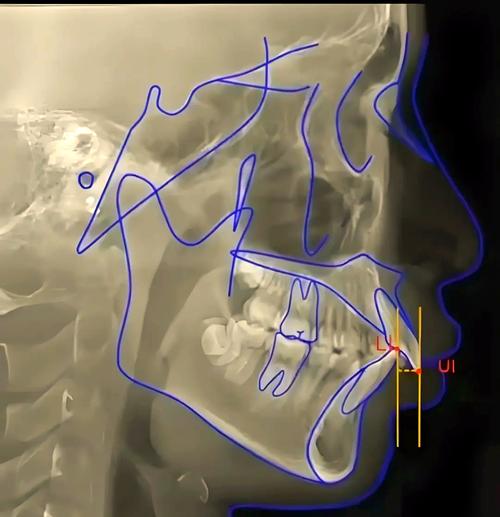

(图片来源网络,侵删) -